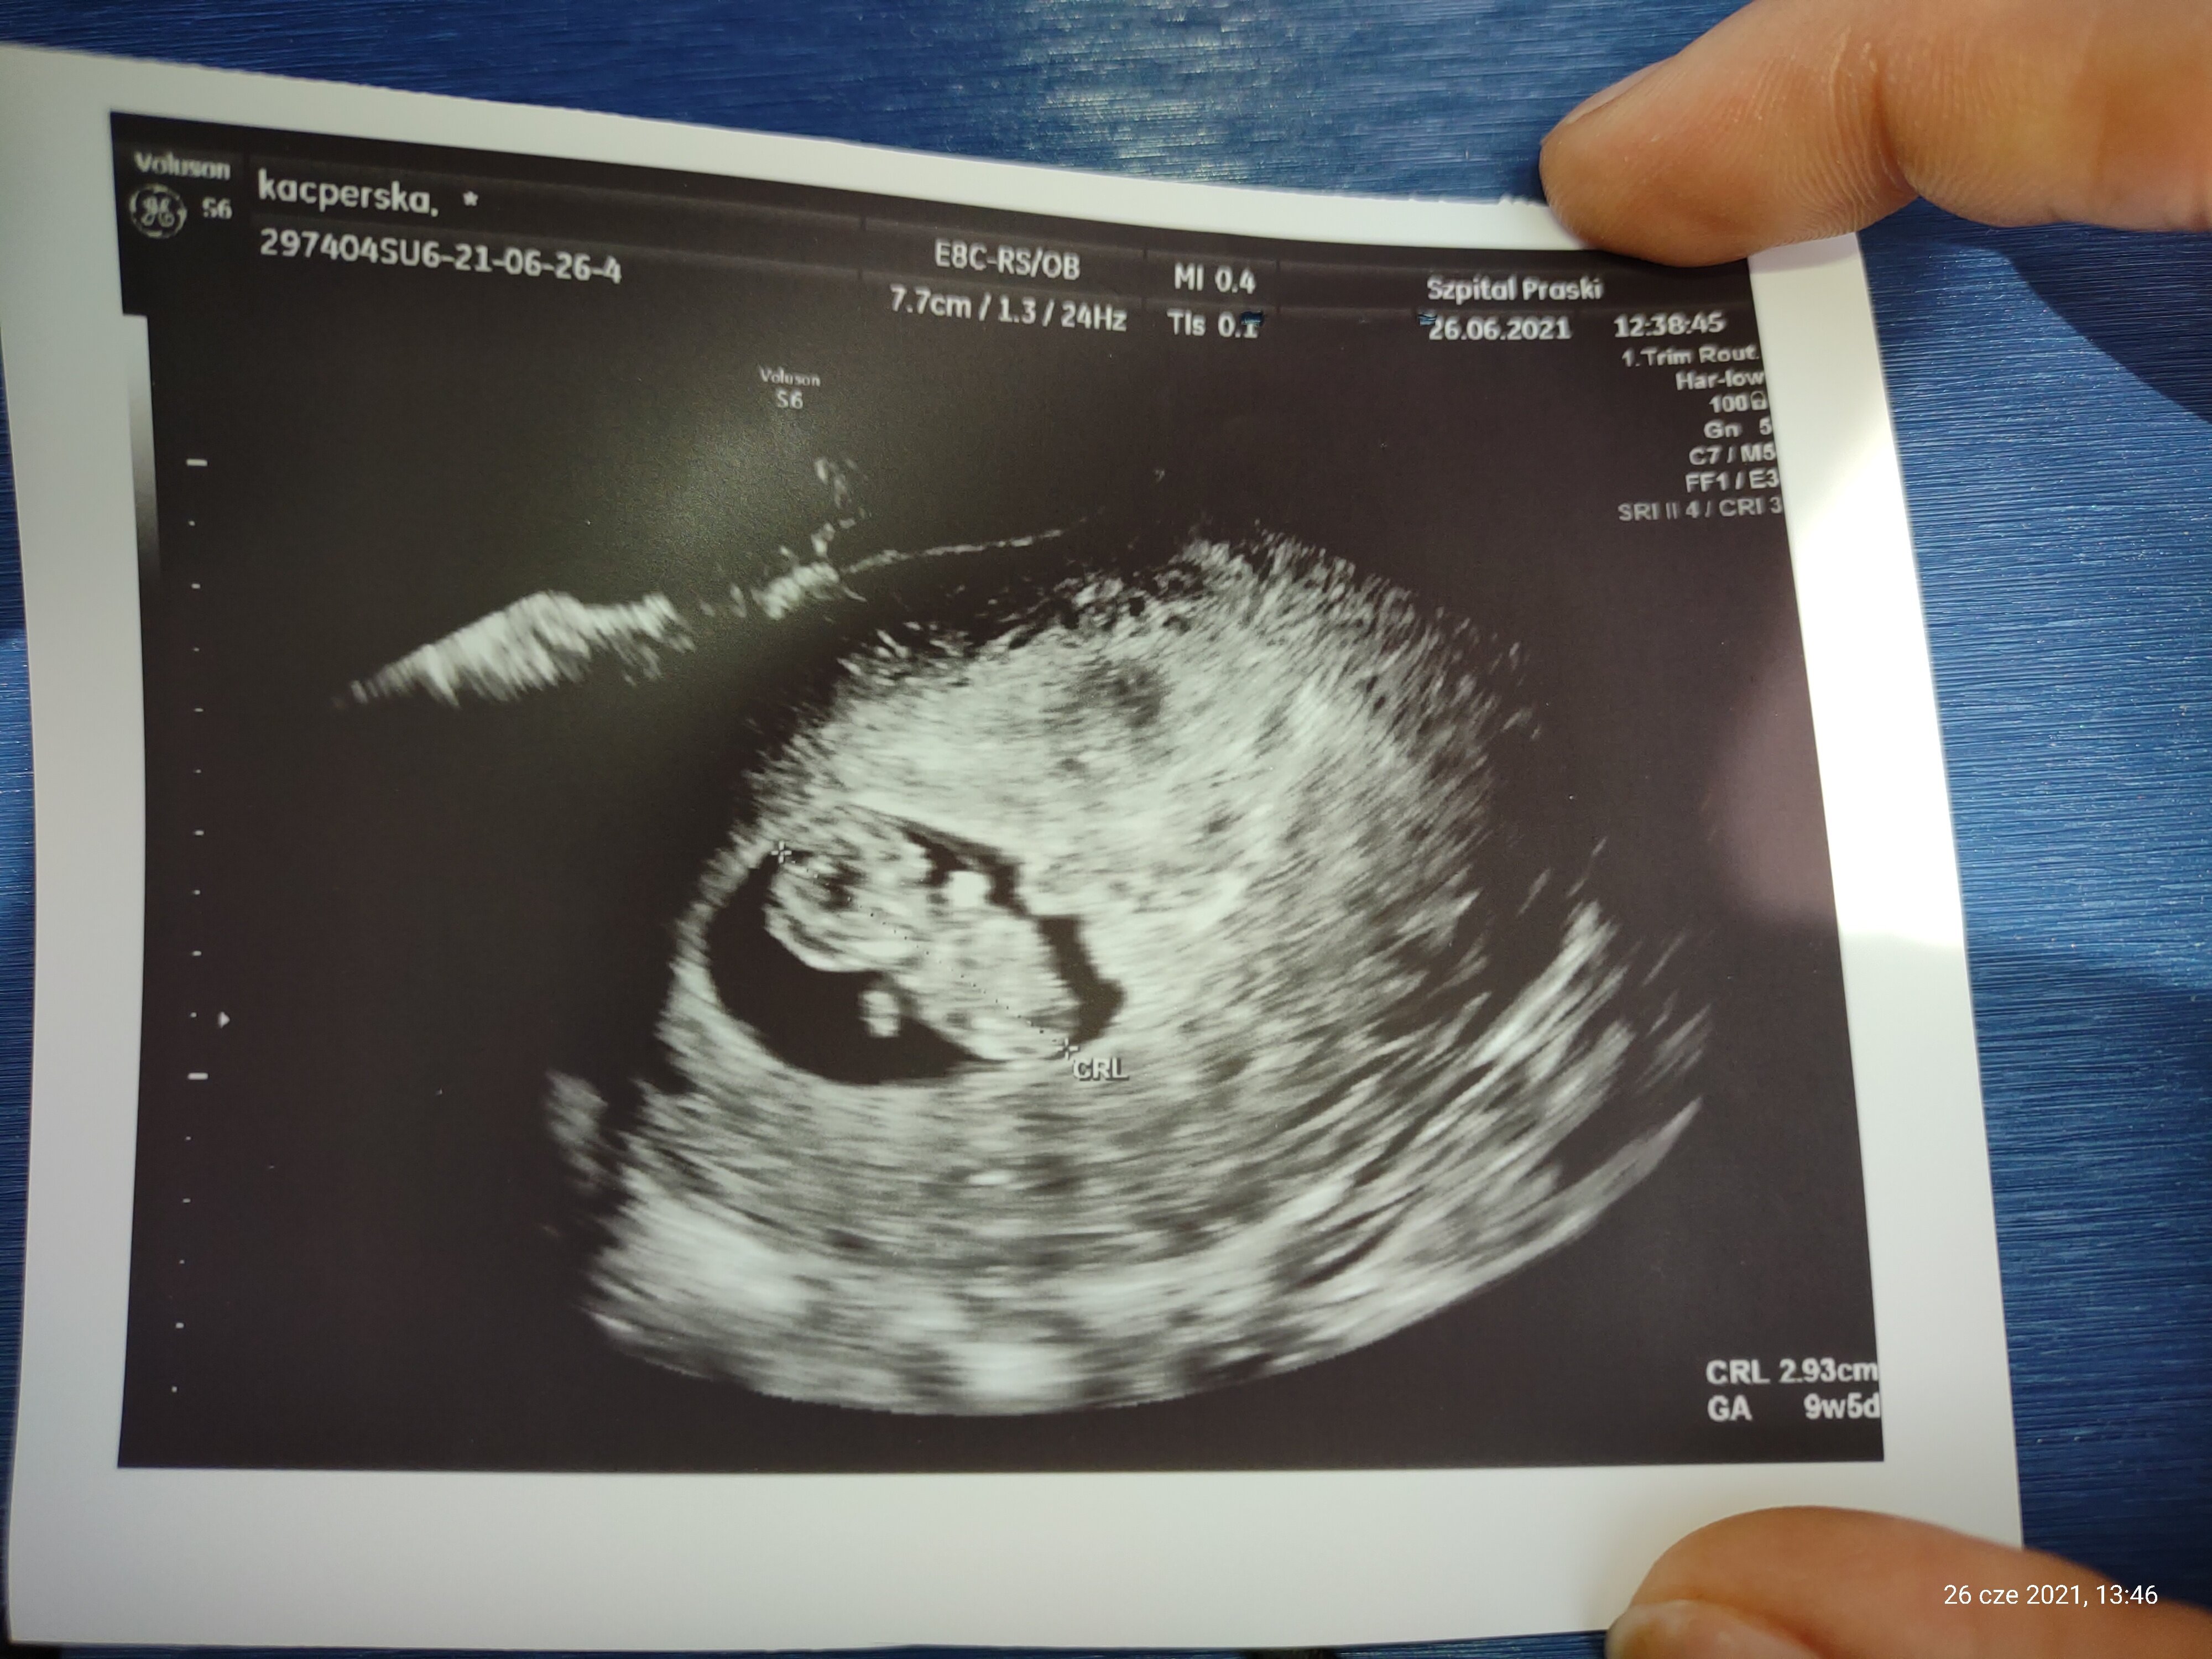

A to moja kruszynka. ❤️❤️❤️

Załączniki

• IMG_20210626_134659481.jpg

IMG_20210626_134659481.jpg

1,1 MB · Wyświetleń: 139